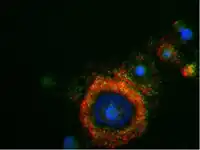

Protein biomarkers are widely used in diagnostics due to their direct involvement in cellular functions and pathways. Protein biomarkers can provide direct information about the functional state of cells and tissues, offering insights into disease mechanisms. Techniques such as mass spectrometry, immunohistochemistry, ELISA, and flow cytometry are employed to detect protein biomarkers, which can indicate protein presence and quantification.[33]

Cellular

Cellular biomarkers allow cells to be isolated, sorted, quantified and characterized by their morphology and physiology. Cellular biomarkers are used in both clinical and laboratory settings, and can discriminate between a large sample of cells based on their antigens. An example of a cellular biomarker sorting technique is Fluorescent-activated cell sorting.[36]